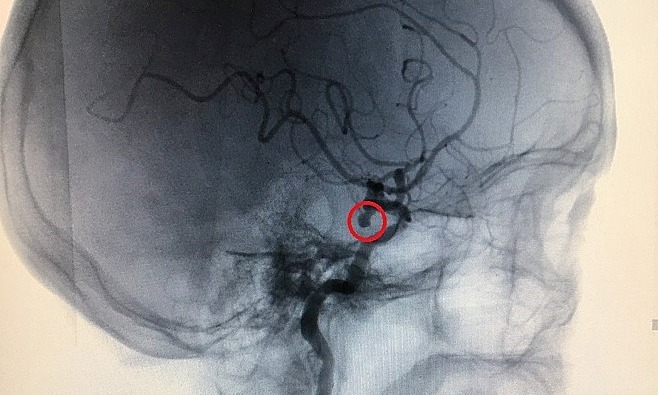

ISUIA (Nghiên cứu Quốc tế về chứng phình động mạch nội sọ) được coi là chứng phình động mạch não không gián đoạn lớn nhất cho đến nay. 1.692 trường hợp phình mạch từ 2 mm trở lên đã được điều trị, trong đó có 1.077 người có kết quả hoàn toàn. Trong 5 năm, không có ai bị vỡ túi phình nhỏ hơn 7 mm ở tuần hoàn trước và nguy cơ vỡ túi phình động mạch chủ sau cao hơn. Tỷ lệ này chiếm khoảng 1,5% vào giữa năm. Nếu túi phình khoảng 7-12mm, đặc biệt khi lớn hơn 12mm thì sk vỡ sẽ tăng lên.

Hiện nay, có 3 lựa chọn để can thiệp túi phình động mạch não không gián đoạn, bao gồm phẫu thuật kẹp túi phình, can thiệp đóng túi phình, điều trị bảo tồn. Hai nghiên cứu phân tích tổng hợp đánh giá kết quả của phẫu thuật kẹp túi phình không gián đoạn, và nhận thấy tỷ lệ tàn tật là 4,1% và 10,9%, và tỷ lệ tử vong là 1% và 2,9 tương ứng là%. Nguy cơ tử vong do phình mạch tuần hoàn sau hoặc phình mạch lớn có thể lớn hơn 20%.

Sau can thiệp bít túi phình, nghiên cứu cho thấy kết quả bất lợi của 3 nhóm can thiệp là 4%; 3 can thiệp Các nhóm Kết quả kém, tỷ lệ tử vong là 1-2% Trong nghiên cứu ISUIA, tỷ lệ tử vong ở nhóm can thiệp là 3,1%. Có túi phình tuần hoàn hoặc túi phình lớn hơn ở phía sau và nguy cơ tử vong là cũng cao hơn. -Điều trị thận trọng bao gồm kiểm soát huyết áp, tránh hút thuốc và uống rượu. Điều quan trọng là theo dõi túi phình bằng kỹ thuật chụp mạch không xâm lấn (như MRA hoặc CTA) sau 6 tháng hoặc một năm để đánh giá sự gia tăng kích thước khối u. Theo dõi. Nếu bạn là lần đầu tiên chọn MRA. Nên lặp lại MRA sau để tránh sai sót giữa hai phương pháp này Đối với những túi phình còn nguyên vẹn nhỏ hơn 7 mm thì đây là lựa chọn hợp lý. Túi có độ nhô ra từ 7 đến 12 mm Nên thận trọng vì hiện nay không có bằng chứng cho thấy can thiệp tốt hơn điều trị bảo tồn. Bệnh nhân trong nhóm này nên được theo dõi kích thước túi phình 6 tháng một lần. Quyết định bắt đầu can thiệp sớm phụ thuộc vào các yếu tố liên quan, chẳng hạn như tuổi, tiền sử gia đình, cơ địa của túi phình, Tăng kích thước,… Hiện chưa có bằng chứng cho thấy việc sử dụng kháng sinh, tập tiểu cầu và chống đông làm tăng nguy cơ vỡ túi phình, do đó, bác sĩ Thắng cho biết, không nên loại bỏ những loại thuốc này, hầu hết các trường hợp là túi phình bảo tồn. Khuyến nghị đối với các nhóm đối tượng có nguy cơ cao, chẳng hạn như gia đình có người nhà bị vỡ phình mạch và bệnh nhân thận đa nang. – Lê Phương